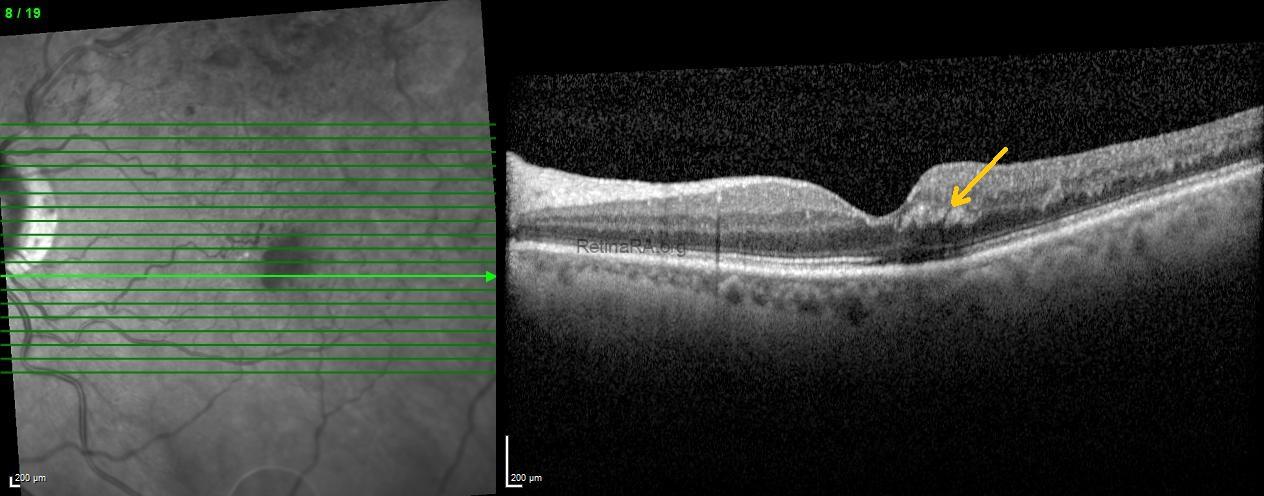

Optical coherence tomography scans passing through the feathery hemorrhages revealed obliquely oriented hemorrhages with shadowing within the Henle fiber layer at the temporal fovea (indicated by arrows).

These findings were consistent with a Henle fiber layer hemorrhage associated with branch retinal vein occlusion. The patient was monitored for spontaneous resolution, with follow-up OCT and FFA planned to assess ischemia and collateral vessel progression.

Henle fiber layer hemorrhage is a distinct type of deep intraretinal hemorrhage localized in the macula, following the oblique orientation of Henle fibers. On fundus examination, it often appears feathery or petaloid, radiating from the fovea, while OCT shows hyperreflective lesions with shadowing in the Henle fiber layer. These hemorrhages are usually associated with vascular disturbances in the deep capillary plexus. Although they can occur in various retinal vascular conditions, Henle fiber layer hemorrhages may also be seen in eyes with branch or central retinal vein occlusion. Recognizing this pattern is important for accurate diagnosis and management.